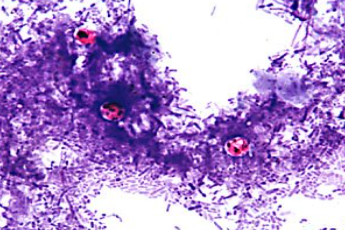

What is the species seen in this photo and WHY?

Entamoeba histolytica troph. RBCs present (cysts CANNOT eat RBCs)